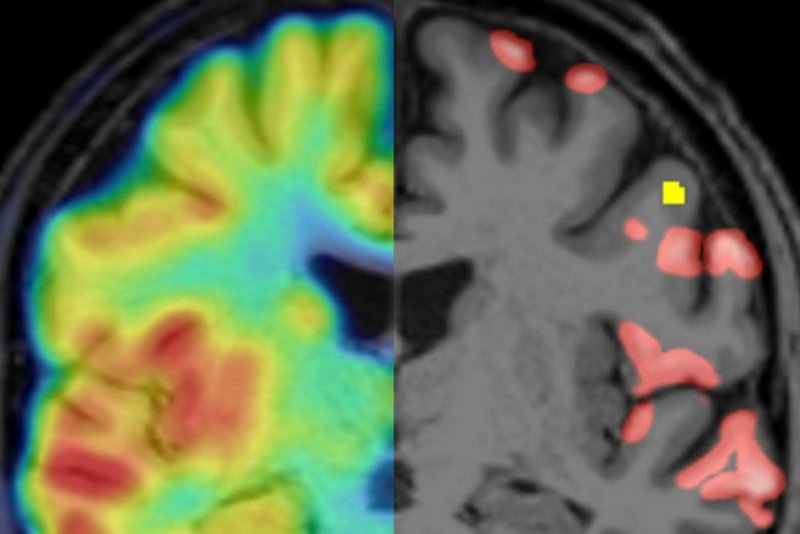

Überlagerung von Synapsen PET und MRT (links) und segmentierte Regionen mit cortikalen Läsionen in der MRT (gelb) sowie reduzierter Synapsendichte (rot)

Überlagerung von Synapsen PET und MRT (links) und segmentierte Regionen mit cortikalen Läsionen in der MRT (gelb) sowie reduzierter Synapsendichte (rot), LMU KLinikum